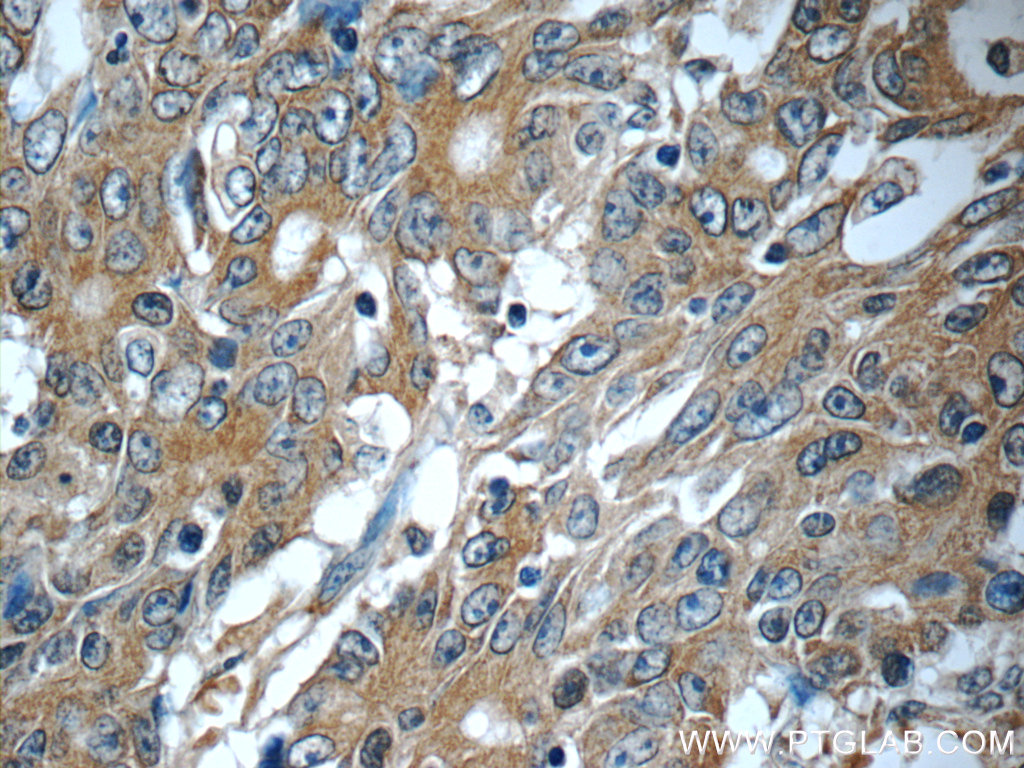

| Positive IHC detected in | human colon cancer tissue Note: suggested antigen retrieval with TE buffer pH 9.0; (*) Alternatively, antigen retrieval may be performed with citrate buffer pH 6.0 |

25721-1-AP targets KIAA0841 in IHC, ELISA applications and shows reactivity with human samples.